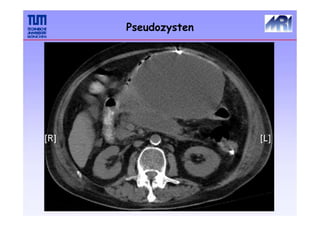

Pseudozysten